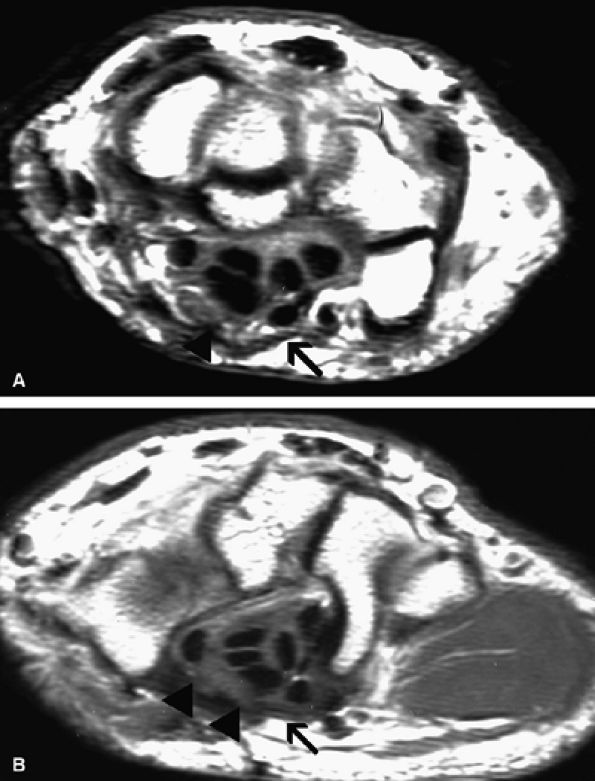

FIGURE 12.19 ● Ulnar neuropathy secondary to compression by hemangioma. An axial post-gadolinium fat-suppressed T1-weighted image shows an avidly enhancing soft-tissue mass encasing (arrowhead) the ulnar nerve (solid arrow) in the medial aspect of the distal arm, consistent with a hemangioma (asterisk). Note invasion of the medial humerus by the mass (open arrow).

FIGURE 12.20 ● Ulnar neurop-athy secondary to scar. Axial T1-weighted (A) and fat-suppressed T2-weighted (B) images demonstrate encasement of the ulnar nerve (arrowhead) by scar tissue (arrows). Selective denervation edema of the flexor carpi ulnaris (fcu) muscle in the proximal forearm is noted.